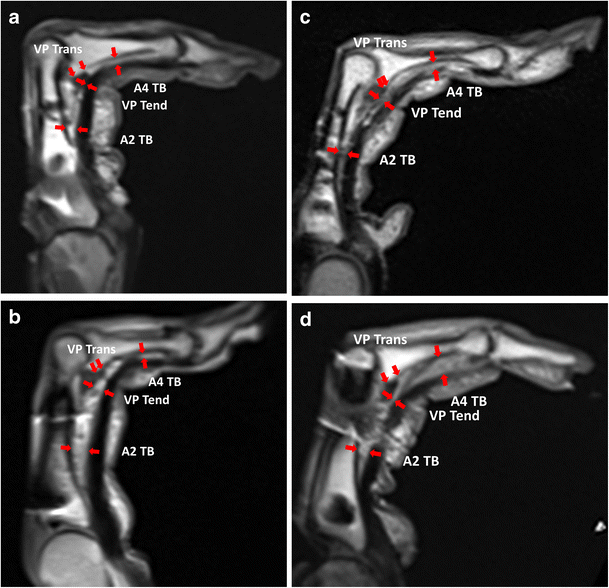

3TMRI of finger pulleys Review of anatomy and traumatic conditions